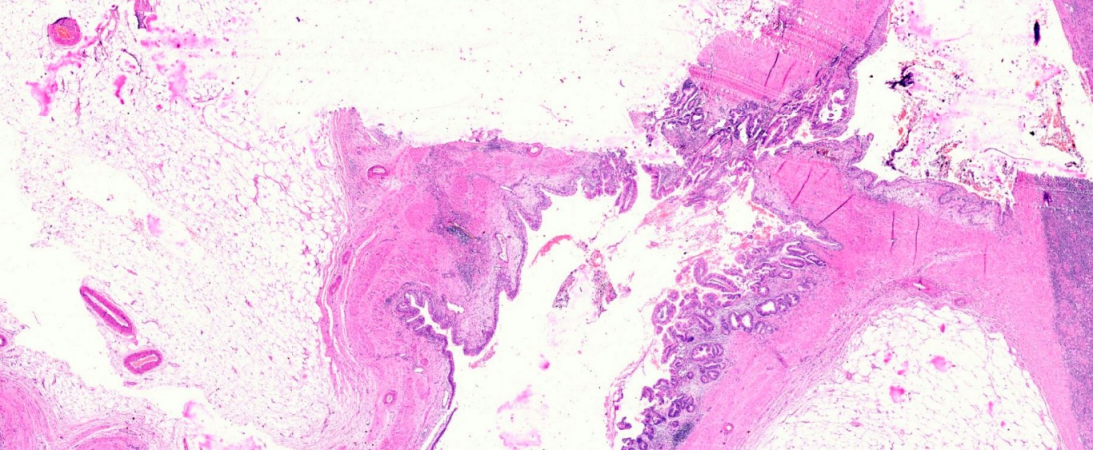

A 31-year-old male of Asian-Indian origin presented to the outpatient department with a one-year history of dull aching right-sided flank pain. There were associated symptoms of abdominal distension and difficulty in voiding urine for the same duration. There was no history of polyuria, graveluria, hematuria or dysuria. On examination, right costovertebral angle tenderness was noted. General and systemic examinations were unremarkable. No lymphadenopathy was noted. On investigation, complete blood count and liver and renal function tests were within normal limits. Urine microscopy showed increased pus cells (20–30/high power field); there were no red blood cells, casts, crystals or malignant cells. Ultrasonography of kidney, ureter and bladder region revealed right-sided hydronephrosis. Computed tomography (CT) scan revealed a hyperdense mass of 2.3x4.6 mm in the right renal pelvis with severe hydronephrosis and cortical thinning (Figure 1 [Fig. 1]). Renal dynamic scan revealed a poorly functioning right-sided kidney. Considering the poor functional status, right-sided nephrectomy was performed and the specimen was sent for histopathological examination. On gross examination, the kidney measured 11x8x5 cm with a cut surface showing dilated pelvicalyceal system filled with slimy watery fluid; the renal pelvis was thickened with a greyish-white cut surface. Multiple stones were noted in the pelvis and kidney parenchyma. Microscopic examination revealed features of chronic pyelonephritis; the adjacent renal pelvis showed pseudostratified columnar epithelial metaplasia with presence of tumor cells arranged in the form of glands and suspended in mucin pools. The tumor infiltrated lamina propria and superficial layers of the muscle coat of the renal pelvis (Figure 2 [Fig. 2], Figure 3 [Fig. 3], Figure 4 [Fig. 4], Figure 5 [Fig. 5]). Adenocarcinoma in situ was noted in the adjacent ureter (Figure 6 [Fig. 6]). Pathological TNM staging was pT2aNxMx.

Figure 2: Scanner view showing mucinous adenocarcinoma involving the renal pelvis (H&E, 20X)

Figure 3: Mucinous adenocarcinoma involving the renal pelvis (H&E, 200x)